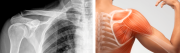

El traumatólogo Abraham Sulcata explicó que la calcificación es la acumulación de cristales de calcio en los tendones del hombro, provocando un dolor agudo en la zona. Esta afección, según Sulcata, aparece por la mala postura o realizar movimientos repetitivos que afecten... + más